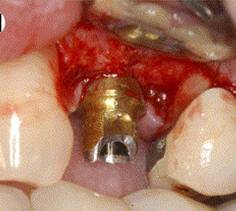

PLACEMENT OF IMPLANT

IMPLANT IN SITU

ABUTMENT PLACEMENT